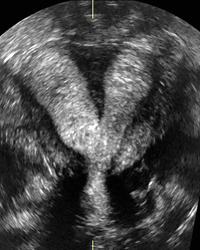

Septated uterus, 3D image.

Septated uterus, pregnancy in left horn, 3D image.

Septated uterus, pregnancy in right horn, 3D image.